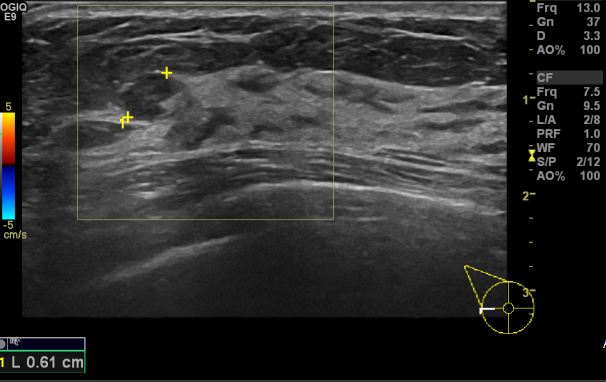

건강검진상 이상소견으로 내원하신 40대 여성분으로 좌측 9시방향에서 5cm 떨어진

거리의 혹 조직검사 시행하여 좌측 유관암 진단 되었습니다.